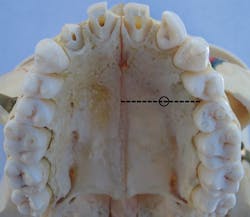

- Insertion site: The insertion site is located midportion of the anterior palate, approximately halfway along an imaginary line connecting the median palatal raphe (tissue overlying the palatal suture) and the palatal free gingival margin between the premolars1,3,4 (see Figure 2).